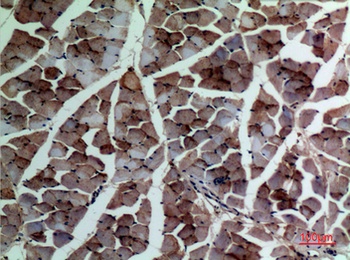

α-SMA Polyclonal Antibody

Catalog Number: orb1411650

| Catalog Number | orb1411650 |

|---|---|

| Category | Antibodies |

| Description | Rabbit polyclonal antibody to α-SMA. |

| Clonality | Polyclonal |

| Species/Host | Rabbit |

| Conjugation | Unconjugated |

| Reactivity | Human, Mouse, Rat |

| UniProt ID | P68133 |

| Tested applications | IHC-P, WB |

| Dilution range | WB: Western Blot: 1/500 - 1/2000. IHC-p: 1:100-300 ELISA: 1/20000. Not yet tested in other applications. |

| Storage | Maintain refrigerated at 2-8°C for up to 2 weeks. For long term storage store at -20°C in small aliquots to prevent freeze-thaw cycles |

| Alternative names | ACTA1; ACTA; Actin, alpha skeletal muscle; Alpha-a Read more... |

| Note | For research use only |